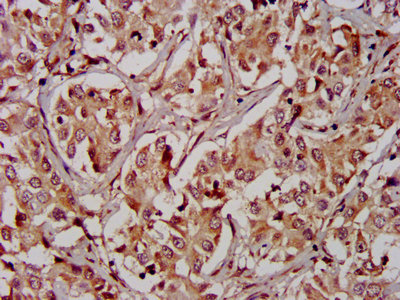

IHC image of CSB-PA019736LA01HU diluted at 1:400 and staining in paraffin-embedded human liver cancer performed on a Leica BondTM system. After dewaxing and hydration, antigen retrieval was mediated by high pressure in a citrate buffer (pH 6.0). Section was blocked with 10% normal goat serum 30min at RT. Then primary antibody (1% BSA) was incubated at 4°C overnight. The primary is detected by a biotinylated secondary antibody and visualized using an HRP conjugated SP system.